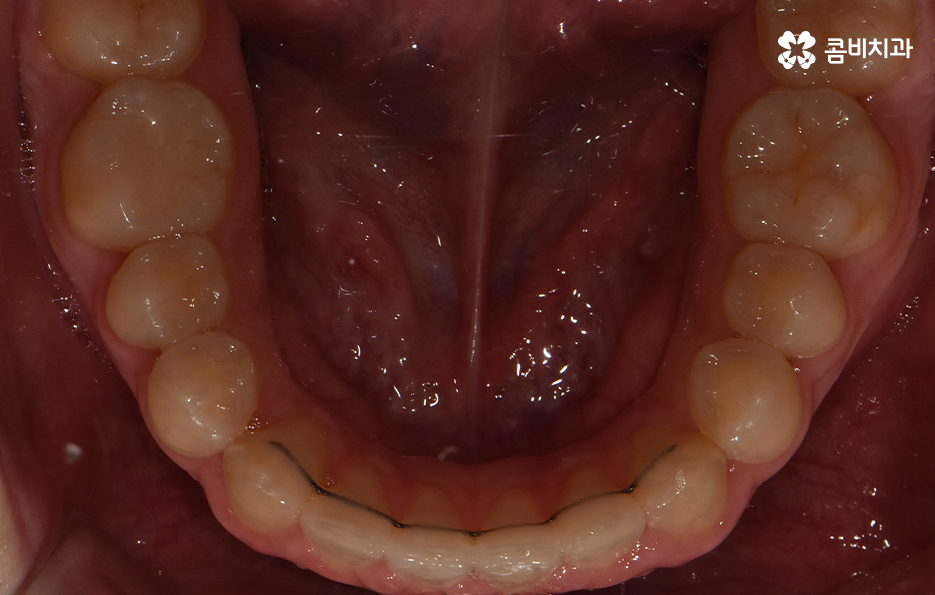

오늘 소개드릴 케이스의 경우 아랫니가 비교적 작기 때문에 교정을 통해 모아주고 윗니의 경우 측면으로 볼 때 더 잘 느껴지겠지만 다소 돌출된 상태이기 때문에 윗니는 발치를 통해 치아 이동 공간을 확보하여 돌출된 앞니를 안쪽으로 모아준 사례로 볼 수 있는데요

아랫니의 경우 치아 사이가 벌어져 있기 때문에 치아를 이동시킬 수 있는 공간이 이미 확보된 상태이고 윗니는 다소 돌출된 앞니를 안쪽으로 들어오게 하면서 심미선을 얼굴형에 조화롭게 맞출 수 있으며 그와 동시에 윗니와 아랫니의 교합도 고려한 치료 계획을 세운 것으로 간단하게 말씀드릴 수 있어요

사진으로 보더라도 아랫니 사이가 눈에 띄게 벌어져 있는 것을 확인할 수 있어요. 보통 웃을 때는 윗니 위주로 보이긴 하지만 아랫니가 이정도로 벌어져 있는 경우에는 콤플렉스로 여겨질 수 있어요

다음으로 교정 장치를 부착한 상태를 보시면 윗니는 양쪽의 치아 하나씩을 발치하였고 아랫니는 치아가 벌어져 있는 공간이 있기 때문에 발치 없이 교정을 진행했어요